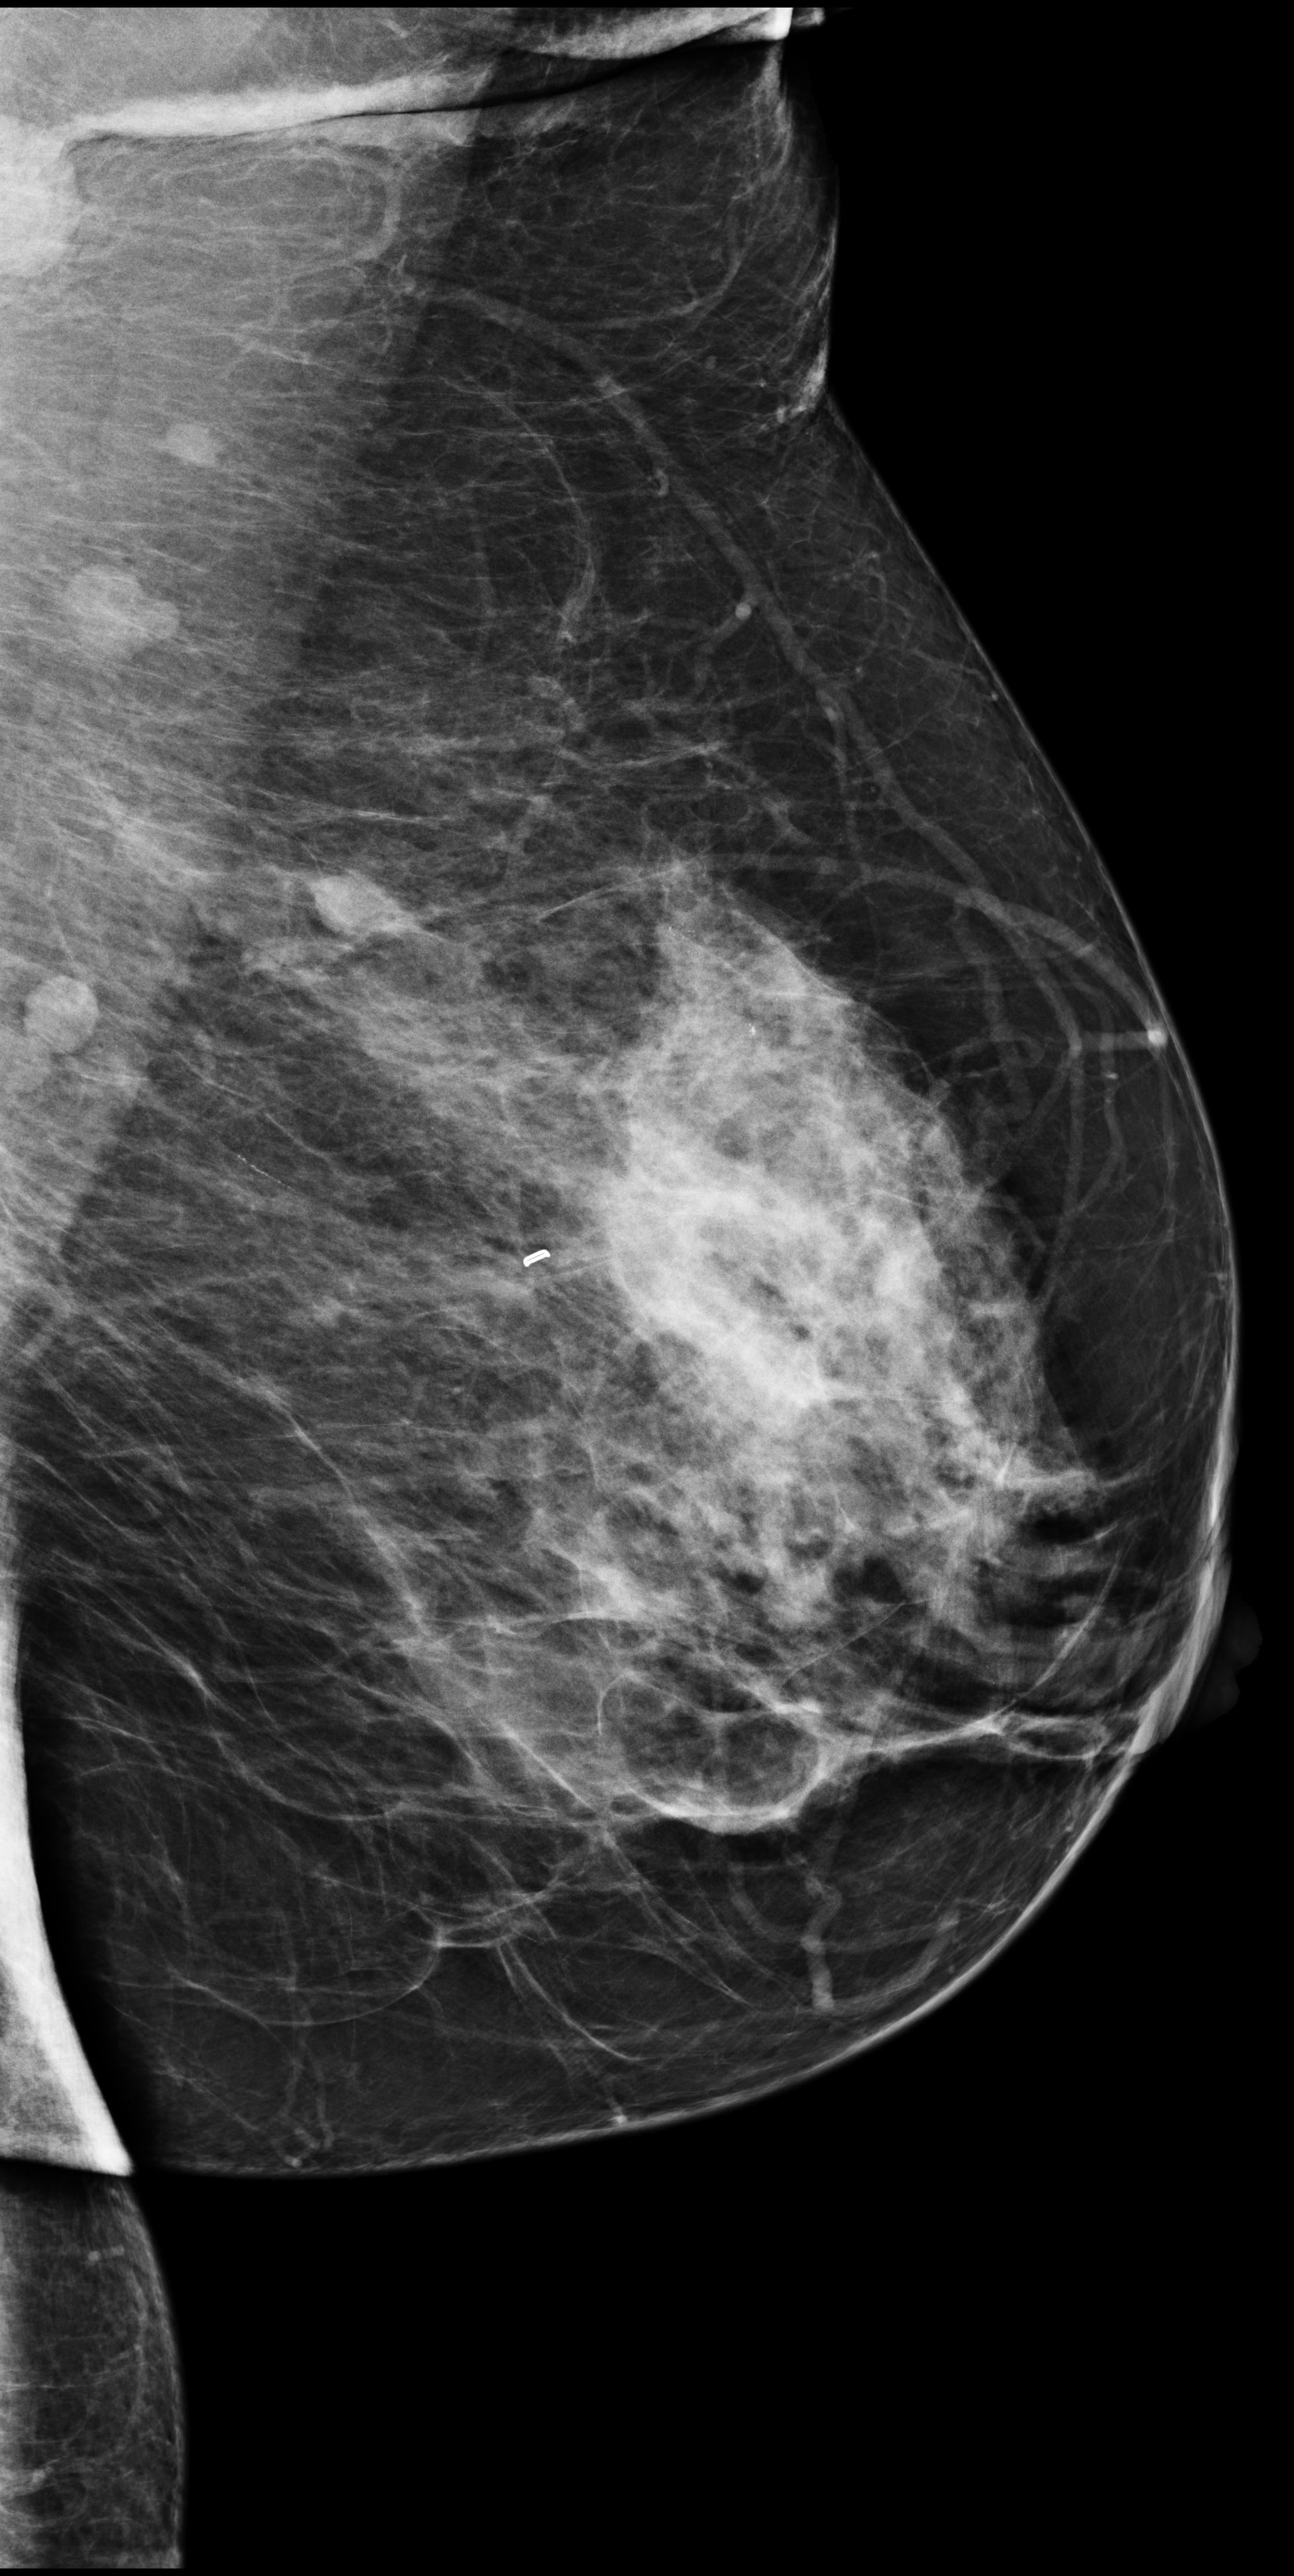

[\capbeside\thisfloatsetupcapbesideposition=left,top,capbesidewidth=6cm]figure[13cm] prior latest highlight prior latest L-CC Refer to caption Refer to caption Refer to caption L-CC Refer to caption Refer to caption L-MLO Refer to caption Refer to caption Refer to caption L-MLO Refer to caption Refer to caption (a) (b)

Figure 3: Test examples where AlignLocalCompare performs better than the single-exam baseline. A breast with a malignant finding shown in (a) (malignant finding is highlighted with red) and one with a benign lesion shown in (b). AlignLocalCompare predicts malignancy with 0.97 probability for (a) and 0.04 for (b), whereas the baseline predicts 0.73 for (a) and 0.24 for (b). There is about a year gap between two exams for both patients.